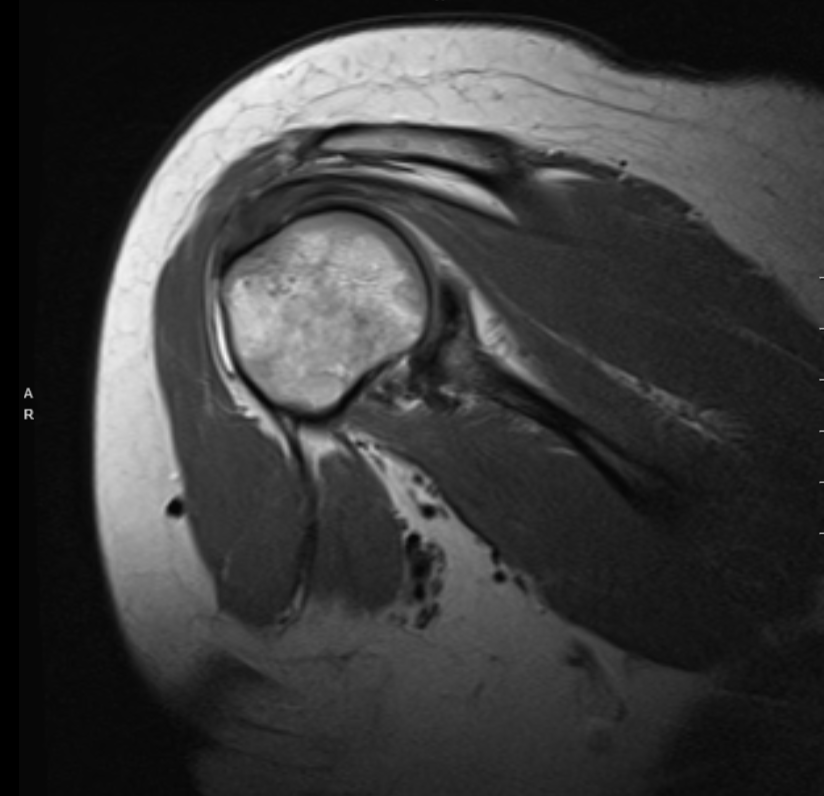

She presented MRI for the right shoulder and showed diffuse tendinosis with a partial thickness tear of the anterior insertional footprint of the supraspinatus tendon. Diffuse tendinosis of the infraspinatus with an interstitial partial delamination tear. Subscapularis tendinosis.

Diffuse superior labral tear/SLAP tear. Tear of the posterior-inferior labrum with partial detachment. Inferior capsular sprain versus adhesive capsulitis. Small effusion. Focal subchondral cyst and focal cartilage defect along the posterior glenoid rim with early subchondral wear pattern.

Subacromial subdeltoid bursitis. Hypertrophic change of the AC joint with Grade I capsular sprain. Edema in the distal clavicle and the acromion which may represent contusion or stress reaction. Narrowing of the subacromial space. Bone marrow edema at the greater tuberosity compatible with bone contusion.

MRI Scan of the right shoulder